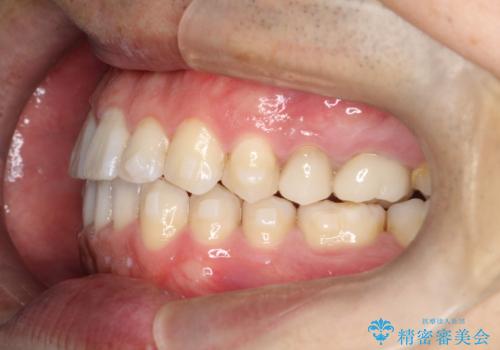

【インビザライン】前歯の隙間を閉じたい

- 前歯の隙間を主訴に来院されました。

マウスピース矯正にて、隙間を綺麗に閉じることができ満足していただきました。

前歯の隙間を閉じる際は、前歯部の突き上げが懸念されるため、適切な治療計画が必要となります。